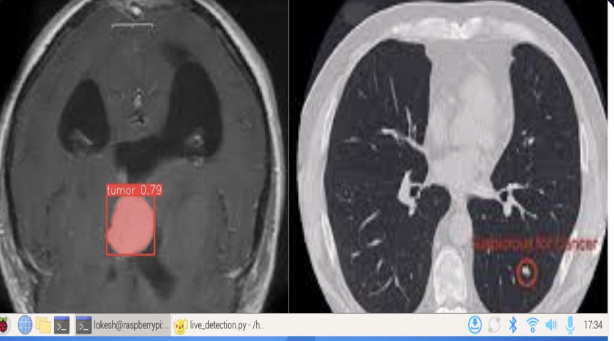

I’m a freelance web developer and UI/UX designer passionate about building modern, user-friendly websites for clients. I specialize in transforming ideas into clean, functional, and visually engaging digital experiences. In addition to web development, I have hands-on experience in deep learning and computer vision, developing intelligent solutions using image and video data. Recognized for innovation with a published patent and as a VISAI competition winner. #FreelanceDeveloper #UIUXDesigner #WebDeveloper #AI #DeepLearning #ComputerVision #PatentPublished #VISAIWinner